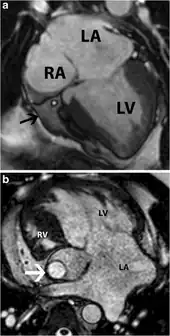

Tricuspid atresia -a) SSFP image indicates absent tricuspid valve replaced by fatty wedge tissue in right AV groove arrow b) tricuspid atresia in individual with dextro-transposition of great arteries this was treated with Fontan shunt arrow